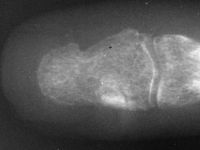

| Case 1. This patient presented with pain with thumb pinch and a sense of fullness in the thumb pulp. Plain radiographs demonstrate an expansile, geographic, radiolucent, juxtaarticular intraosseous mass, typical for an enchondroma. There is circumferential cortical thinning and possible cortical breaks. |